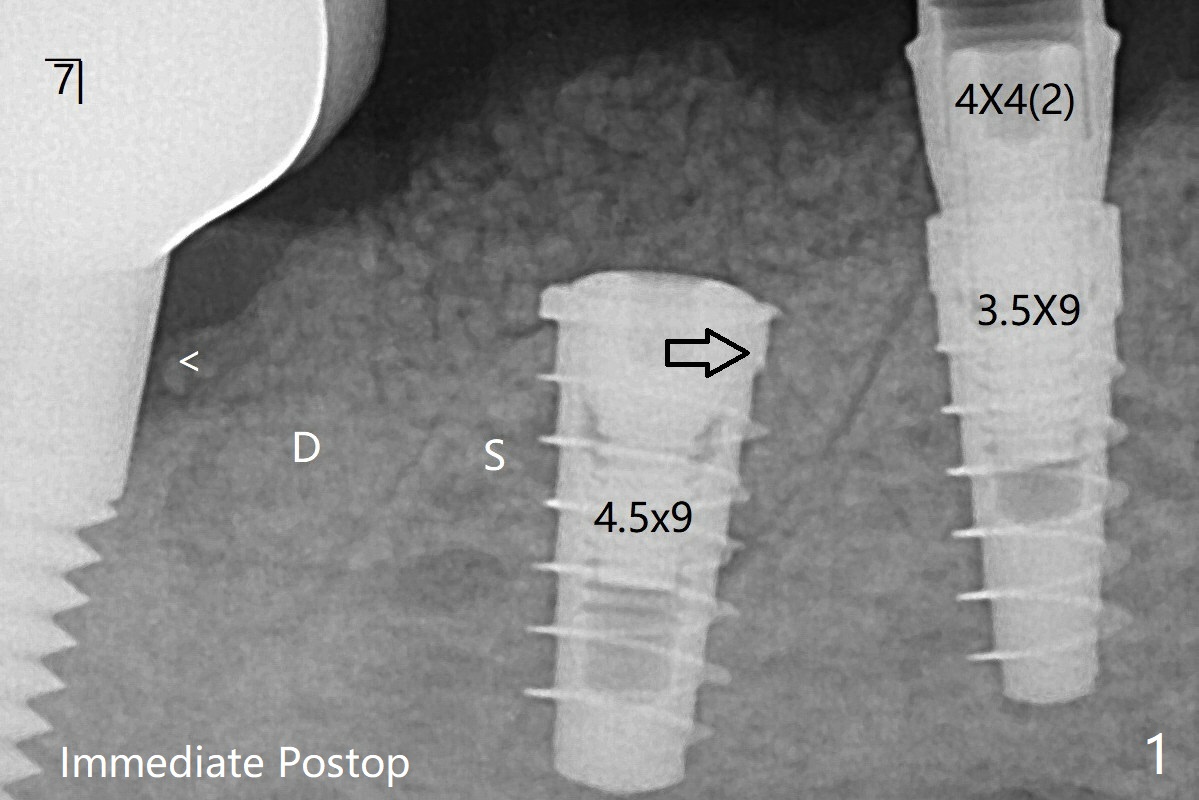

术后四个月6放置基台后(图六),制作连体5,6牙冠,垫高(打开咬合),近中衬里,推4,关闭3,4之间间隙(图三)。6植体远中第一个螺纹好像暴露。